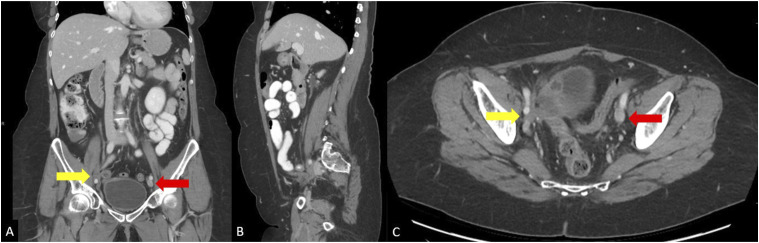

回腔静脉血栓形成和流出梗阻是一种有许多可能原因的疾病,通常表现为与静脉充血或不全有关的症状。最近的设备发展和血管内支架置入术和静脉成形术对生活方式限制症状的可用性难以保守治疗,导致对这些手术的兴趣增加。虽然静脉支架置入的几种常见并发症已经有了很好的描述,但一种罕见和紧急的并发症是附近动脉压迫或闭塞。在此,我们报告2例髂静脉再通和支架置入后发生髂动脉闭塞的病例,并讨论可能导致这种罕见并发症的因素。

Ileocaval venous thrombosis and outflow obstruction is a condition with many possible causes that typically presents with symptoms related to venous congestion or insufficiency. Recent device development and availability of endovascular stenting and venoplasty for lifestyle-limiting symptoms refractory to conservative management has led to increased interest in these procedures. While several common complications of venous stent placement have been well-described, 1 uncommon and emergent complication is nearby arterial compression or occlusion. Here we present 2 cases of iliac artery occlusion occurring after iliac venous recanalization and stenting, and discuss possible factors that may contribute to this uncommon complication.